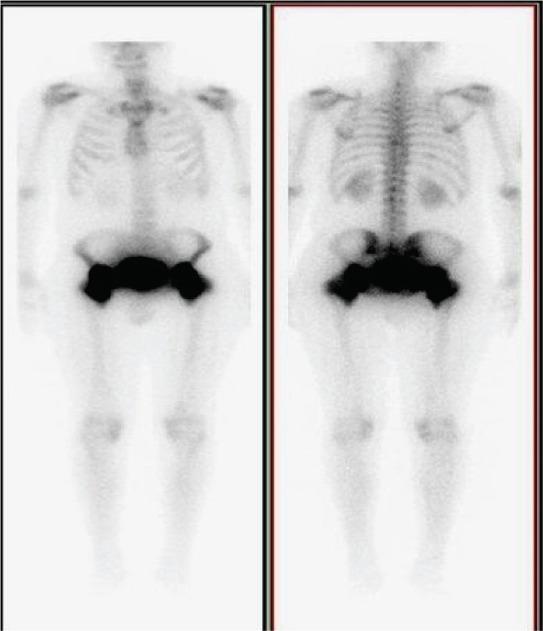

Neurogenic heterotopic ossification (NHO) is an abnormal development of bone in extra-skeletal tissues, related to neurological disease. NHO is frequently seen after traumatic brain injury or spinal cord injury. NHO may also occur as a rare complication of Guillain Barre Syndrome (GBS). Here, we present a 39 year old man with an acute onset of GBS who developed NHO around both hips two months after the disease onset. Our patient had a history of mechanical ventilation, incomplete tetraplegia and prolonged immobilisation. The pathogenesis of NHO is unclear. Various risk factors have been associated with the development of NHO; prolonged coma, long-term sedation, spasticity, degree of paralysis. NHO is a rare complication of GBS and physicians should be aware that it can develop especially in patients with severe paralysis and in need of mechanical ventilation. Pain and restriction of movements, especially in the hips, should bring NHO to the mind.

神经源性异位骨化(NHO)是一种骨骼外组织中骨骼的异常发育,与神经系统疾病有关。NHO 常发生在颅脑损伤或脊髓损伤后。NHO 也可能是吉兰-巴雷综合征(GBS)的罕见并发症。在此,我们介绍了一位 39 岁男性,他患有急性 GBS,在发病两个月后出现双侧髋关节周围 NHO。我们的患者有机械通气、不完全四肢瘫痪和长时间固定的病史。NHO 的发病机制尚不清楚。各种危险因素与 NHO 的发生有关;昏迷时间长、长期镇静、痉挛、瘫痪程度。NHO 是 GBS 的罕见并发症,医生应注意到,它可能特别发生在严重瘫痪和需要机械通气的患者中。疼痛和运动受限,尤其是在臀部,应引起对 NHO 的关注。